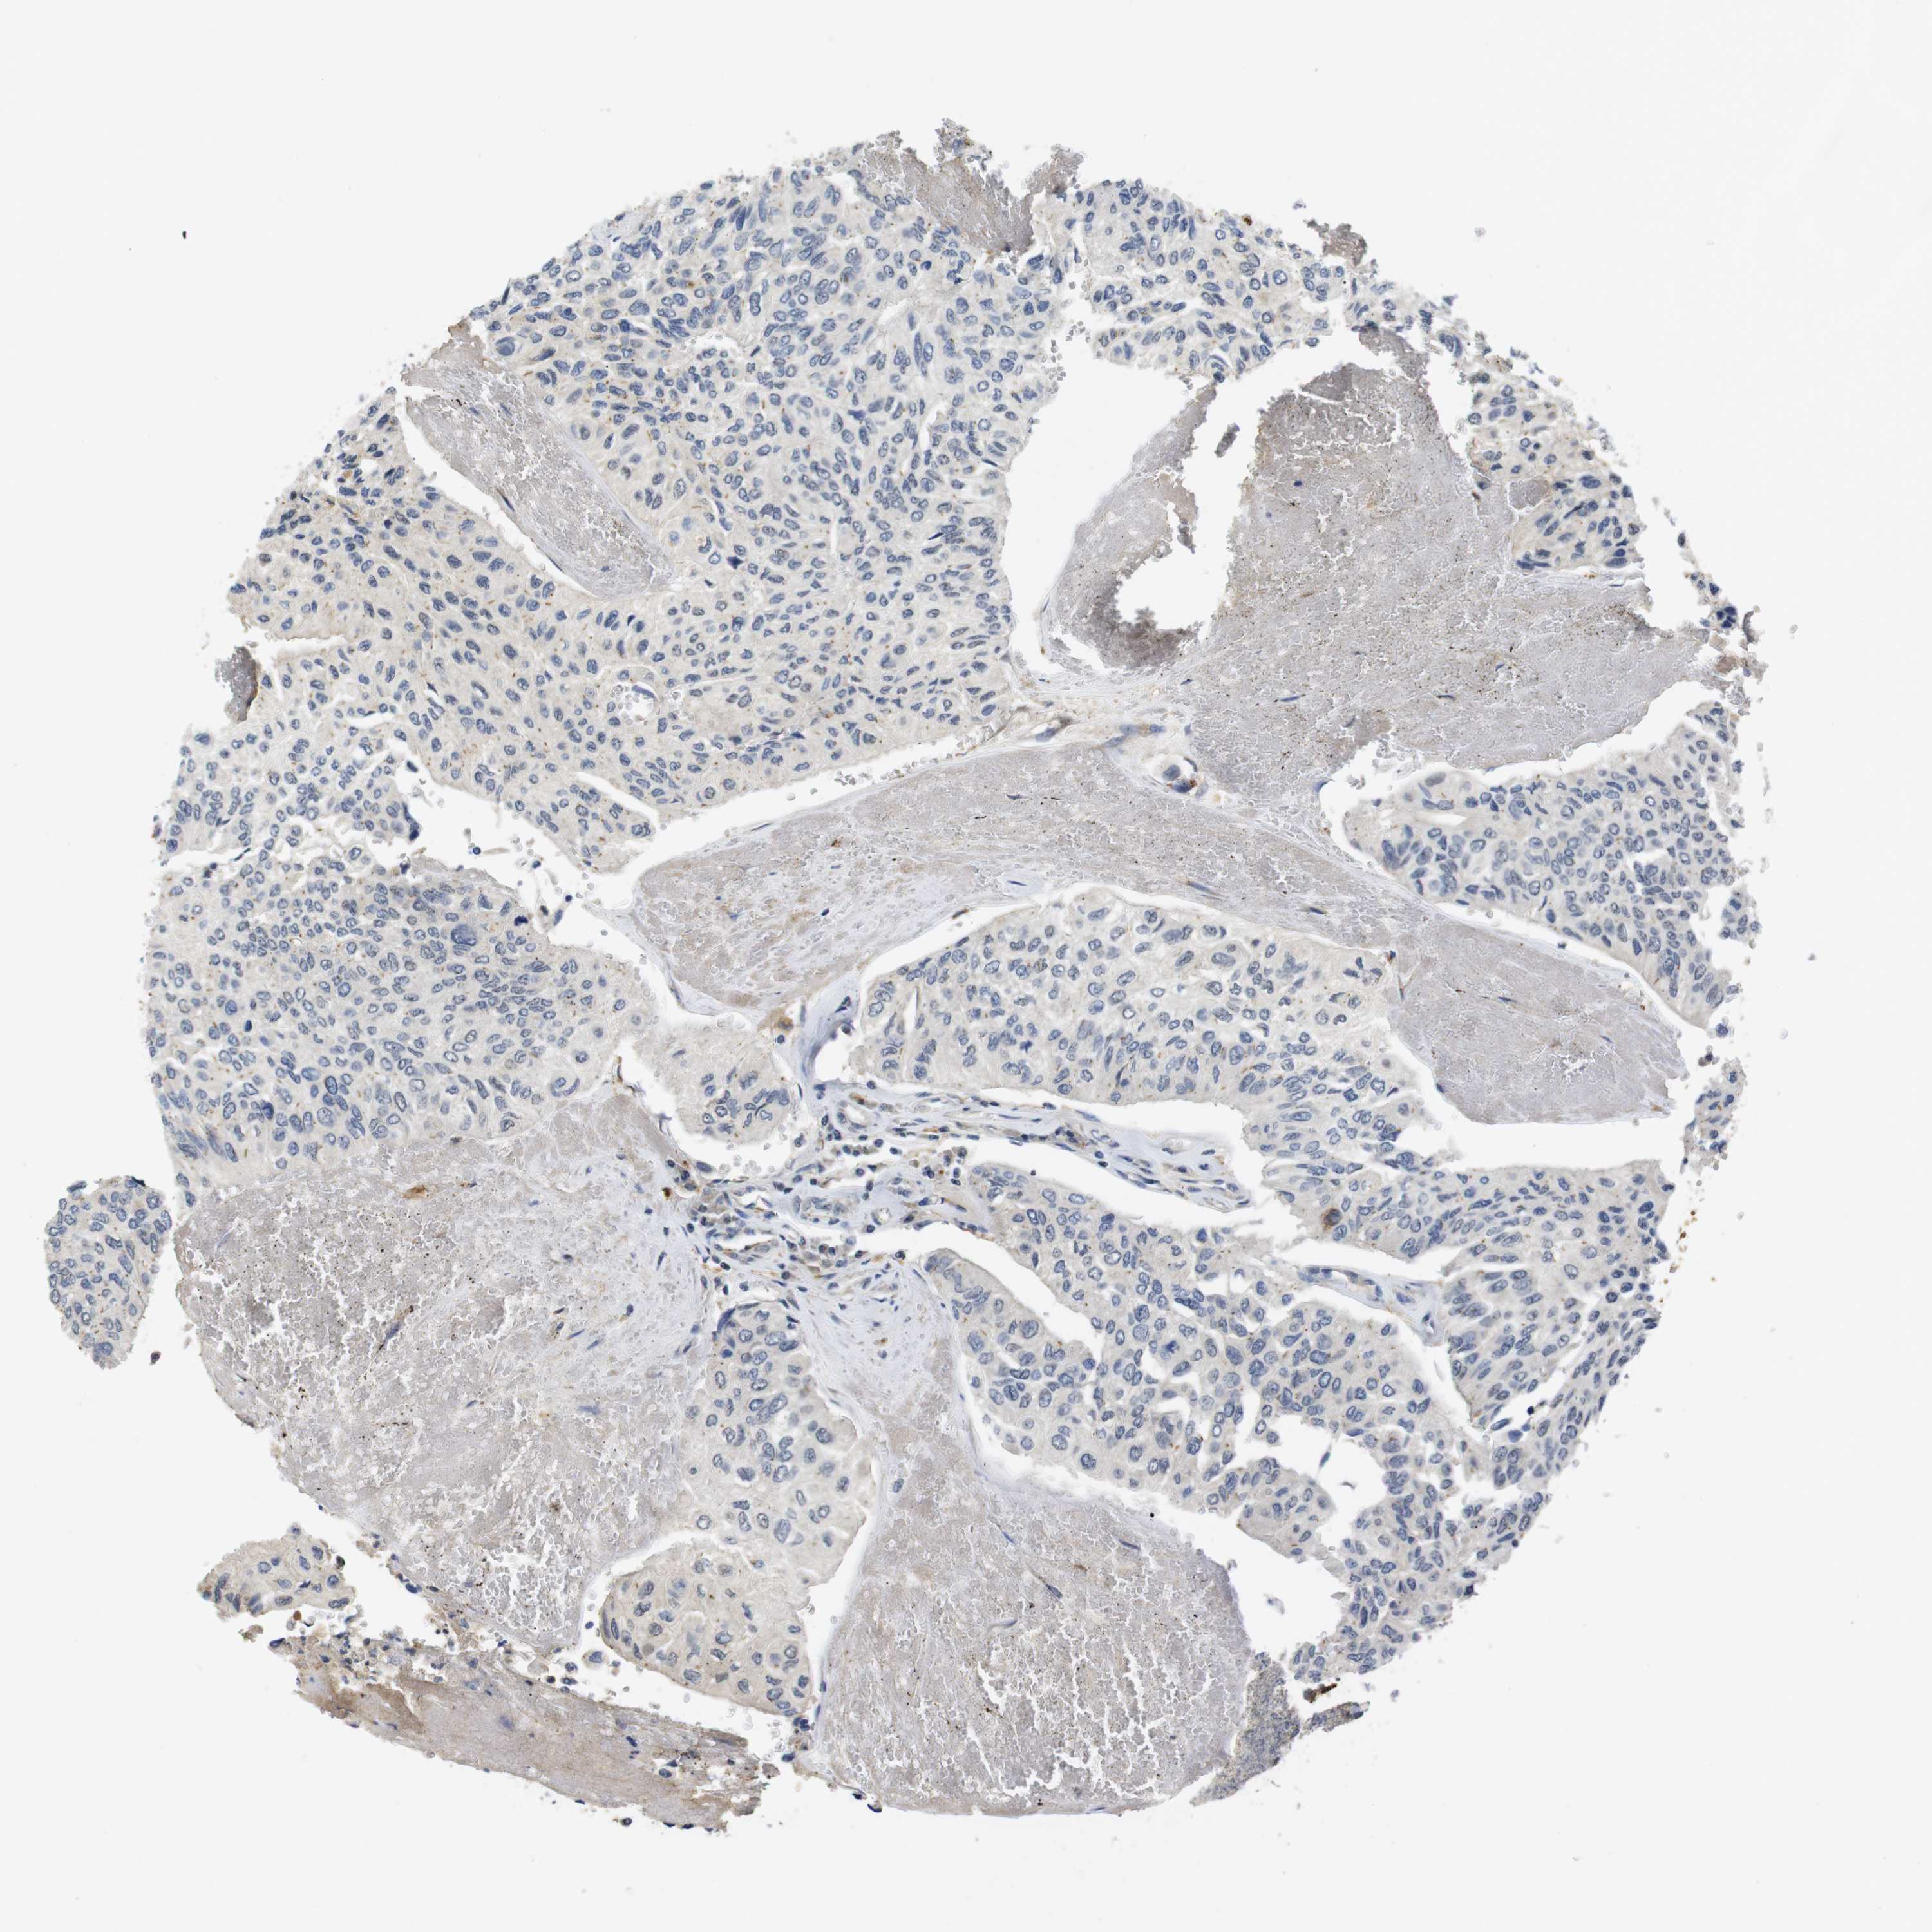

UROTHELIAL CANCER - Protein expressioni

A mouse-over function shows sample information and annotation data. Click on an image to view it in a full screen mode. Samples can be filtered based on level of antibody staining by selecting one or several of the following categories: high, medium, low and not detected. The assay and annotation is described here.

Antibody stainingi

Antibody staining in the annotated cell types in the current human tissue is reported as not detected, low, medium, or high, based on conventional immunohistochemistry profiling in selected tissues. This score is based on the combination of the staining intensity and fraction of stained cells.

Each image is clickable and will lead to virtual microscopy that enables deeper exploration of all samples and also displays staining intensity scores, fraction scores and subcellular localization as well as patient and tissue information for each sample.

Antibody HPA018830

Antibody CAB010149

Staining

High

Medium

Low

Not detected

Intensity

Strong

Moderate

Weak

Negative

Quantity

>75%

75%-25%

<25%

None

Location

Nuclear

Cytoplasmic/membranous

Cytoplasmic/membranous,nuclear

Urothelial carcinoma, Low grade

Urothelial carcinoma, High grade